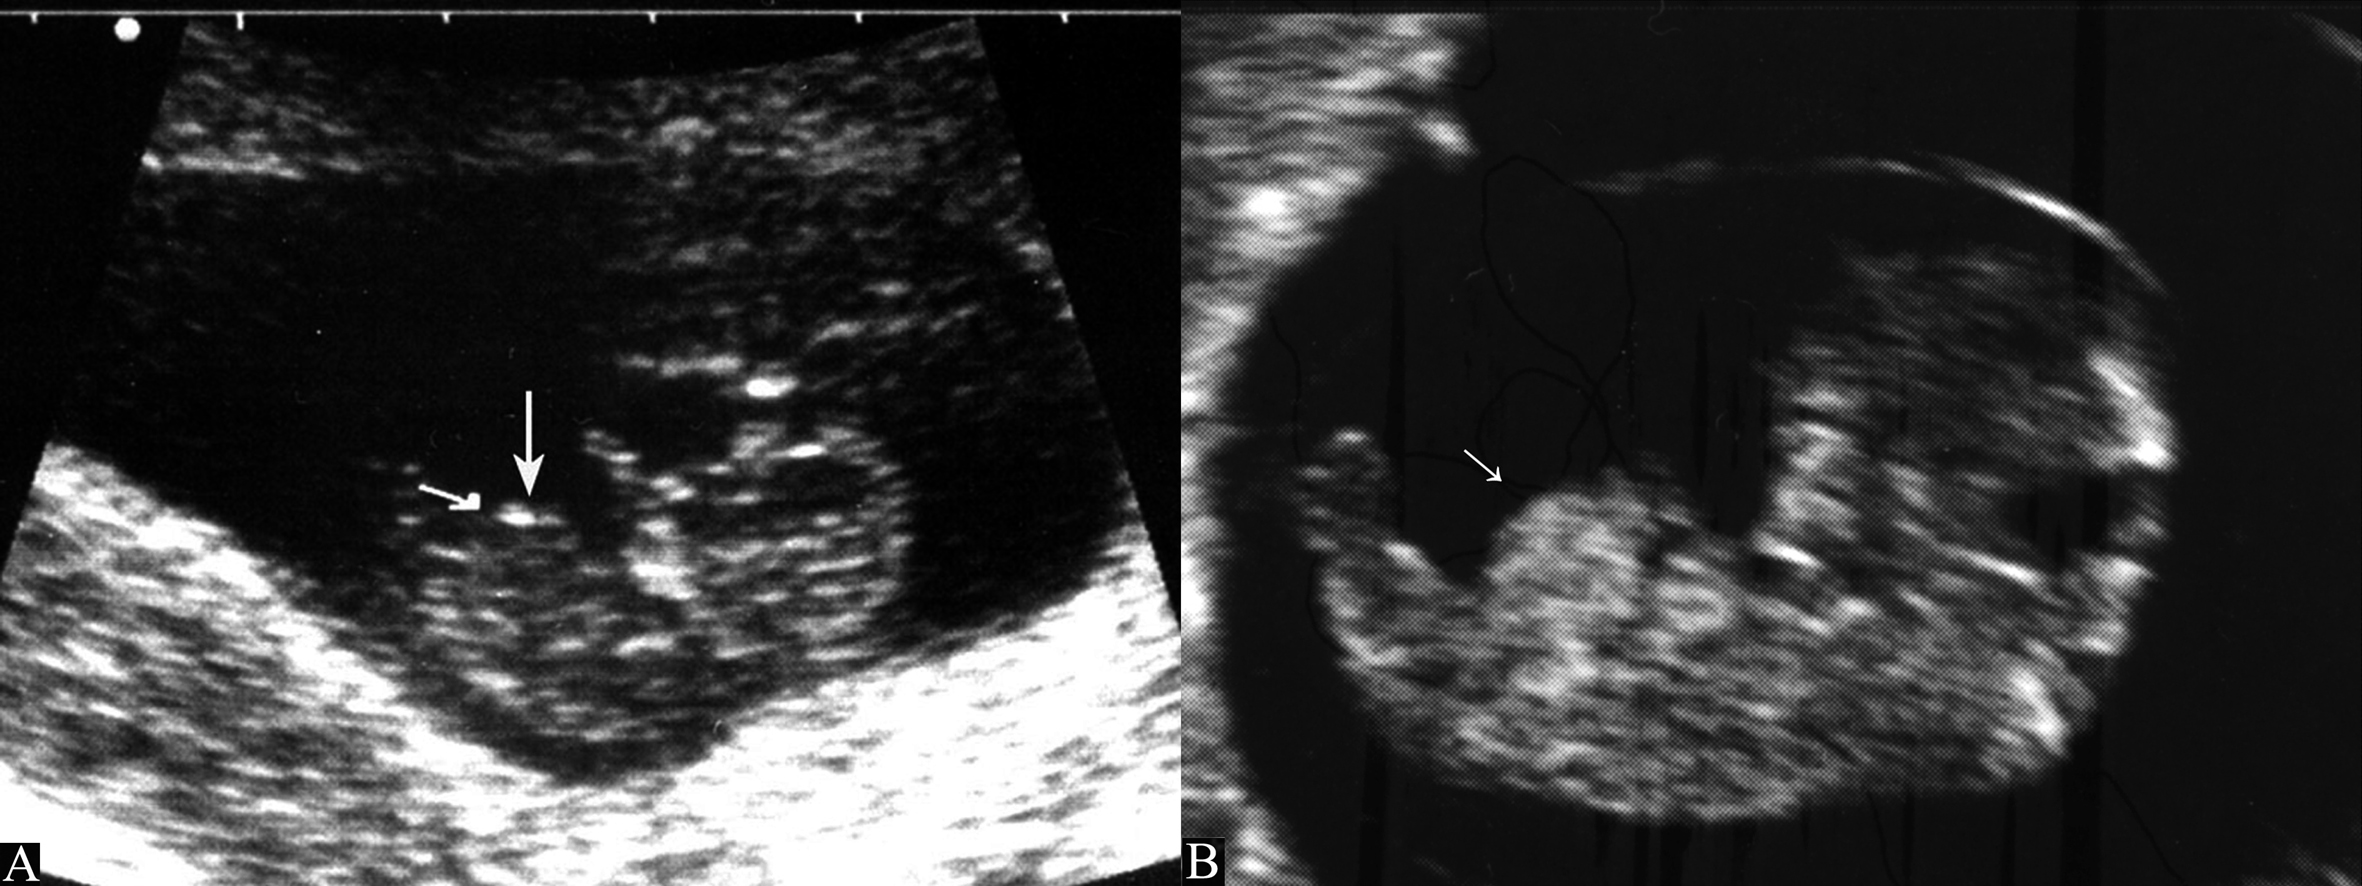

在胚胎的发育过程中中肠生长速度明显快于胚胎腹腔的发育速度。随着中肠的增长,其向腹侧弯曲形成“U”型的肠袢突向胚胎脐部引起脐部突出,形成“生理性前腹壁中肠疝”(图2)。这种情况发生在胚胎第8周,是中肠移向绒毛膜腔的正常表现。此时,绒毛膜腔通过脐部与胚胎体内相通,腹腔内由相对固定、体积较大的肝脏、肾脏占据,不能再容纳生长较快的中肠,以致于其“疝入”脐带内。到第12孕周以后,胎儿腹腔容积迅速扩大,疝入脐带内的中肠返回腹腔,生理性前腹壁疝消失。经腹超声显像检查在第8孕周、CRL15mm~22mm 时显示脐部突出,突向体外大约6mm~9mm,此即“中肠疝”,在第9孕周、CRL 23mm~31mm 时,突出达到最大并可逐渐缩小至5mm~6mm,第10孕周~12孕周时,多数“中肠疝”消失,但直至第12孕周末,仍可有20%的胎儿脐部可显示突出,随着胎儿的生长,脐部突出逐渐缩小、消失。如果中肠不能正常返回并在原疝囊处发育,则形成脐疝。

图2 箭头示生理性前腹壁疝